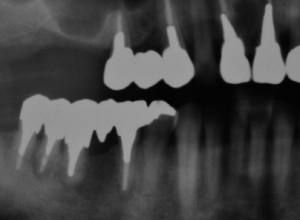

症例1

初診時のレントゲン写真。

治療後2年経過。根の先の黒い影が消えています。

治療後3年経過。適切な根管治療を行い、咬み合わせを再構築しました。